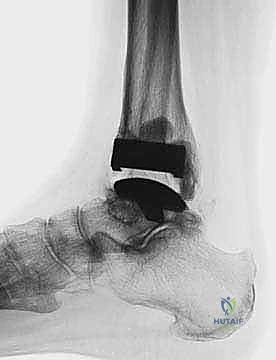

FIG 6 • The TNK ankle replacement for rheumatoid arthritis of the ankle (cemented replacement). A. Preoperative AP view. B. Preoperative lateral view. C. Postoperative AP view 2 years 6 months after the surgery. D. Postoperative lateral view.